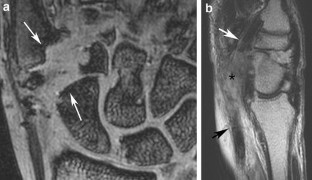

Results

Five of the patients showed evidence of triscaphe osteoarthritis. One of the patients showed synovitis and reactive marrow edema at the triscaphe joint without more specific findings of osteoarthritis. Five patients showed evidence of FCR tenosynovitis. Partial-thickness tears were noted in three patients. Two patients showed complete discontinuity of the FCR; one of them had undergone prior tendon harvesting for interposition arthroplasty after trapezectomy. One patient showed a ganglion cyst in connection to the FCR tendon sheath.

The FCR tendon courses over the volar surfaces of the scaphoid and trapezium in a separate fibro-osseous tunnel. This anatomical and functional relationship explains the coexistence of FCR tendinopathy and STT arthritis demonstrated by MR imaging.